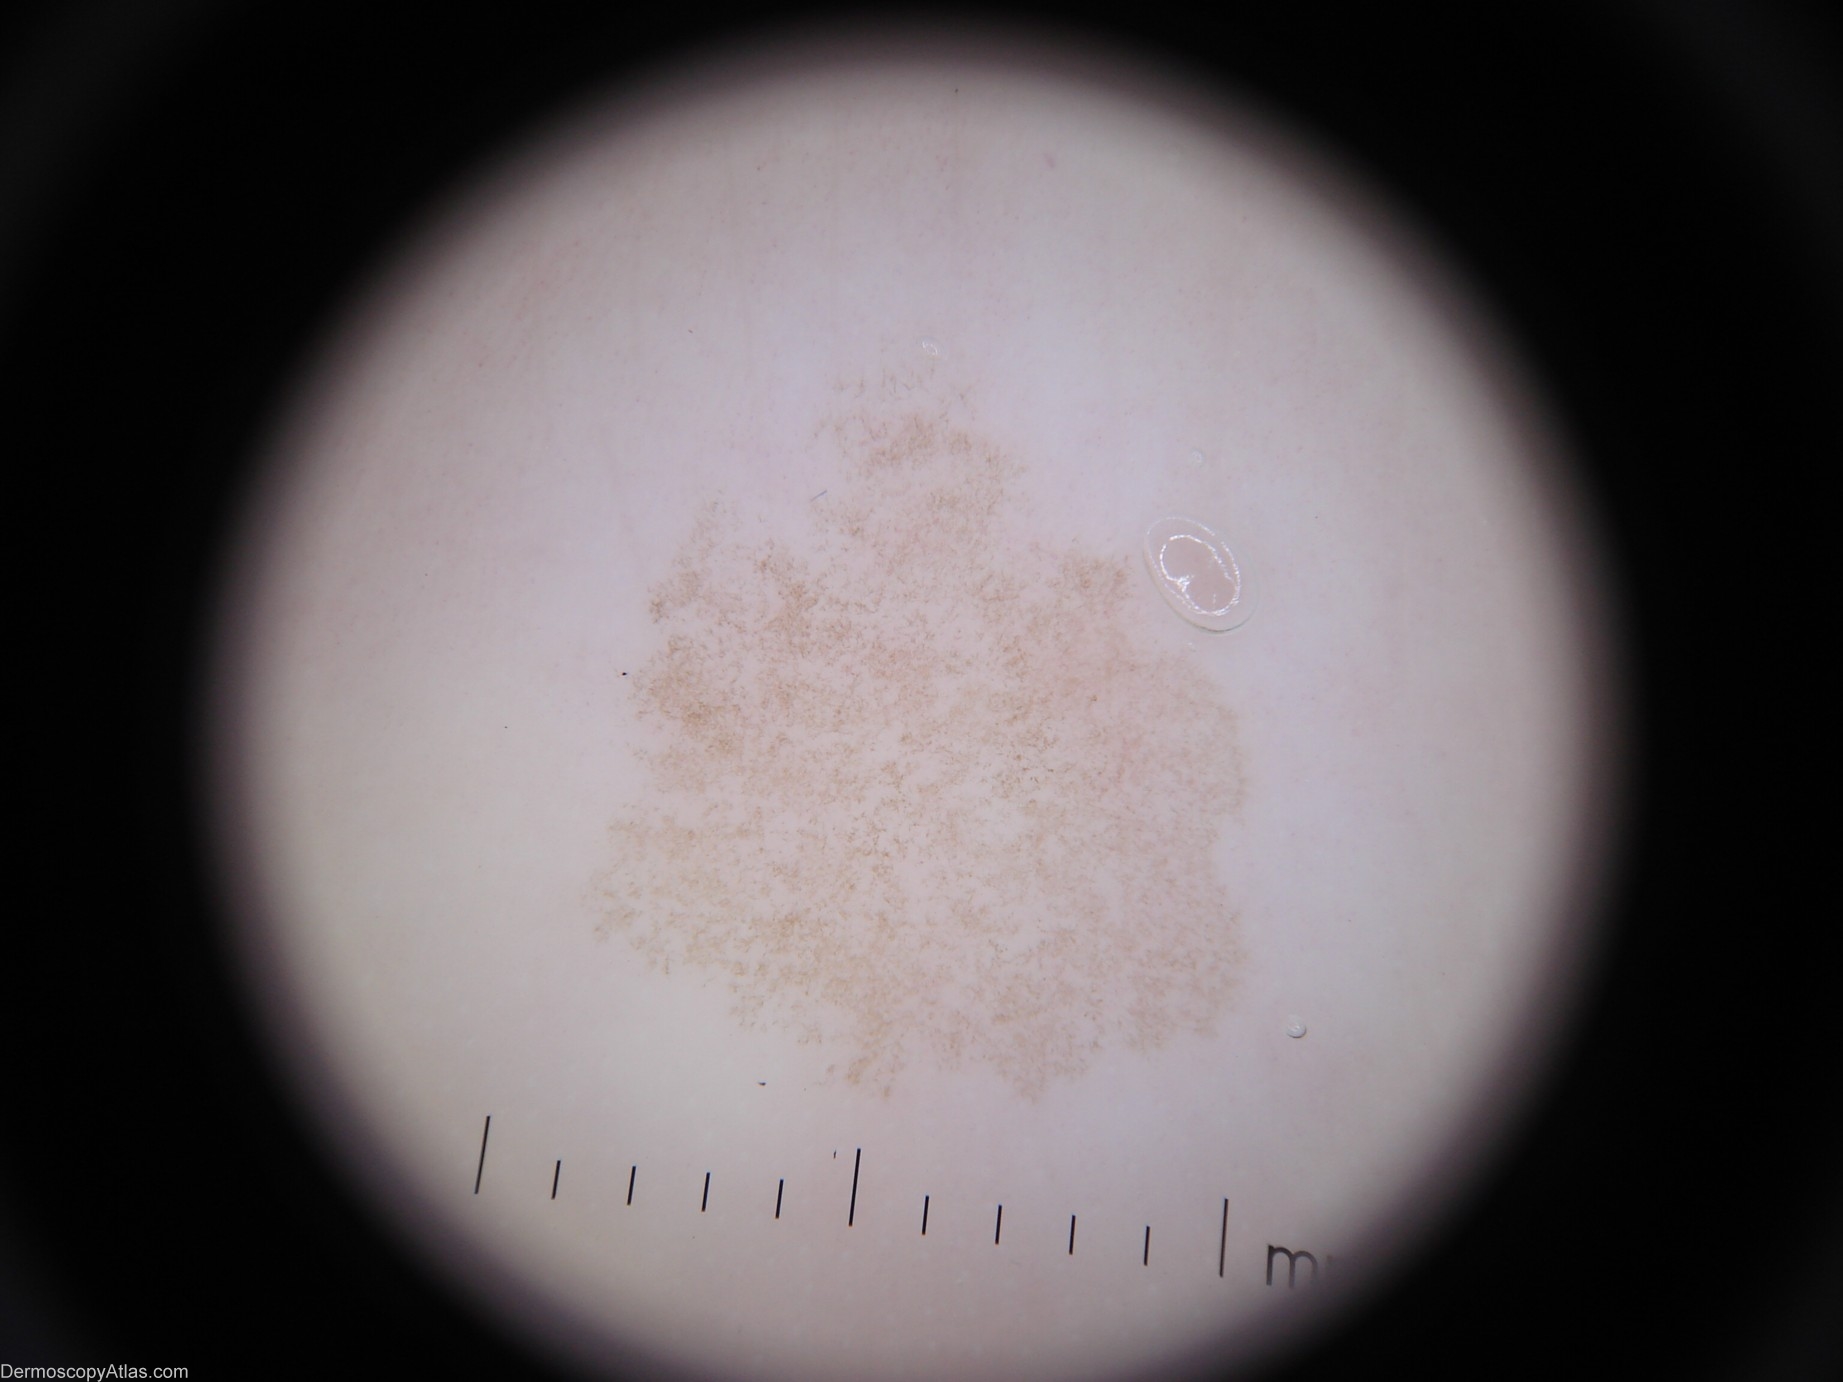

Image Number #2691 (Tinea nigra)

Site: Foot,dorsum

Diagnosis: Tinea nigra

Description: Dermoscopy - There is one colour. Pigment pattern is symmetrical. The pigment appearance is "soft" like a thin veneer of frost on glass. There is no reticular network. The Pseudo-network present is produced by branching hyphae in the stratum corneum of the epidermis. It has neither lines-reticular nor lines-curved. The adjective I would use is "crystalline".

This 42 year old lady with a past history of melanoma presented for a routine skin check and this lesion was encountered

This condition is caused by Exophiala werneckii. It is most commonly found on the palms or palmar surfaces of the fingers and less commonly the plantar or lateral surfaces of the feet. ( Ref Skin Pathology - Weedon 2nd edition page 674)